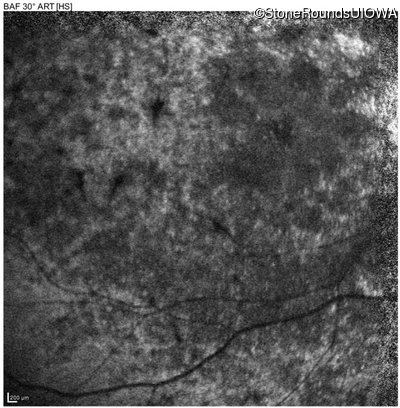

AR Stargardt Disease (IIA)

Age at visit: 8 years

This 8 year old girl had normal vision until age 6 when she failed a school vision screening. That year, she was able to play softball well, but this year she often loses sight of the ball and is often hit by it.

AR Stargardt Disease ABCA4 IVS38-10T>C IVS38-10T>C AR